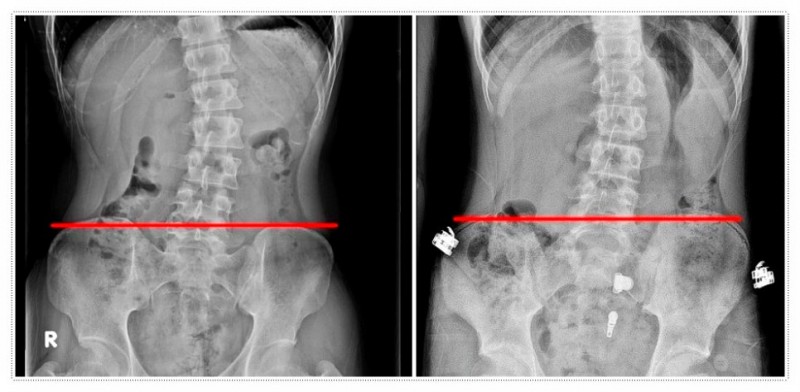

척추는 뒤에서 보았을 때 반듯한 일직선이어야 합니다.

하지만 여러 요인으로 인해 S자나 C자 형태로 휘는 척추측만증이 나타나기도 합니다.

그래서 초기에 엑스레이로 각도를 정확히 확인하는 것이 무엇보다 중요합니다.